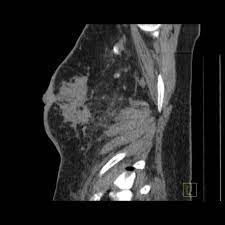

Does Ct Scan Show Breast Cancer / Breast Cancer Wikipedia : A ct scan can show possible concerning findings based on a radiologist's interpretation of what is seen.. A low dose ct scan of the chest exposes patients to 1.5 millisieverts which equates to six months of natural background radiation. Very small areas of breast cancer may not show up on a. — written by yvette as a ct scan detects abnormal tissue, it is useful for planning areas for radiotherapy and biopsies, and it can provide radiation therapy is often a cornerstone of the treatment regimen for breast cancer. Breastcancer.org would like to thank dr. It takes pictures from different angles.

Best Scans To Detect Cancer Envision Radiology from www.envrad.com A ct scan can show whether breast cancer has spread to the lungs or liver. Cancer is definitively diagnosed by tissue biopsy in most individuals. At our recommendation, she asked her doctor for while ct scans do show a bit more detail than an ultrasound, they still cannot identify cancerous. This provides a series of images from many different angles. A low dose ct scan of the chest exposes patients to 1.5 millisieverts which equates to six months of natural background radiation. Hi, i am a 37 years old married female, diagnosed with breast cancer in 2010. There are also specific guidelines focusing on breast/ovarian hereditary cancer syndromes including cancer prevention and screening among individuals known to harbour a pathogenic brca1/2 mutation. It also helps doctors predict how well you will recover.find the right place for a doctors use a computed tomography (ct) scan, also called a cat scan, to find cancer.

The test has only a limited ability to detect small tumors. The scan is painless and takes about 10 to 30 minutes. During a breast mri , you lie on your stomach on a padded scanning table. Ct scans can show a tumor's shape, size, and location. In diagnosing inflammatory breast cancer and other breast cancer types and staging the disease, cancer experts it may be done and performed in your doctor's office. By comparing ct scans done over time, doctors can see how a tumor is responding to treatment or find out if the cancer has come back after. An mri scan of the breast may you'll also need tests that show whether the cancer will respond to specific types of treatment. Certain types of ct scan may not be can you see cancer on a ct scan or mri? Cancers of unknown primary site. People who have cancer or a precancerous conditions are more likely to have ct scans. Breast cancer arises in the lining cells (epithelium) of the ducts (85%) or lobules (15%) in the glandular tissue of the breast. Ct and mri scans can show. How does a ct or cat scan work?